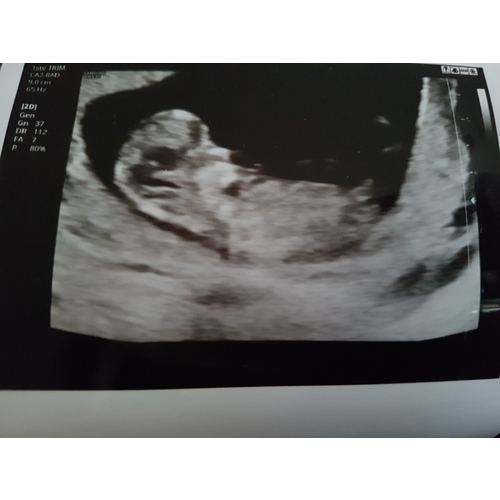

11+5. Ik dacht laten we een gokje wagen 😂

Niks te zien nog?

Te klein, te ver, te vroeg..

De navelstreng loopt er ook nog eens langs 😉

Moeilijk te zien.. maar hebben jullie een idee misschien? Nog 8 dagen.. dan ...

De nub is goed verborgen achter het beentje maar ik gok op boy 💙